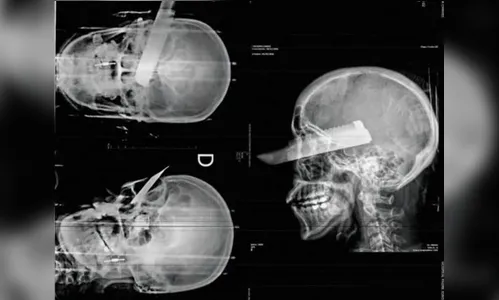

Autor A faca foi cravada no olho direito da mulher - Foto: Polícia Civil

Um homem foi preso em flagrante na última segunda-feira (2) suspeito de tentar matar a companheira em São Carlos, no Oeste de Santa Catarina. Durante o ataque, a vítima foi atingida por um golpe de faca que ficou cravado em seu olho direito. Apesar da gravidade do ferimento, a mulher sobreviveu e conseguiu buscar socorro com vizinhos.